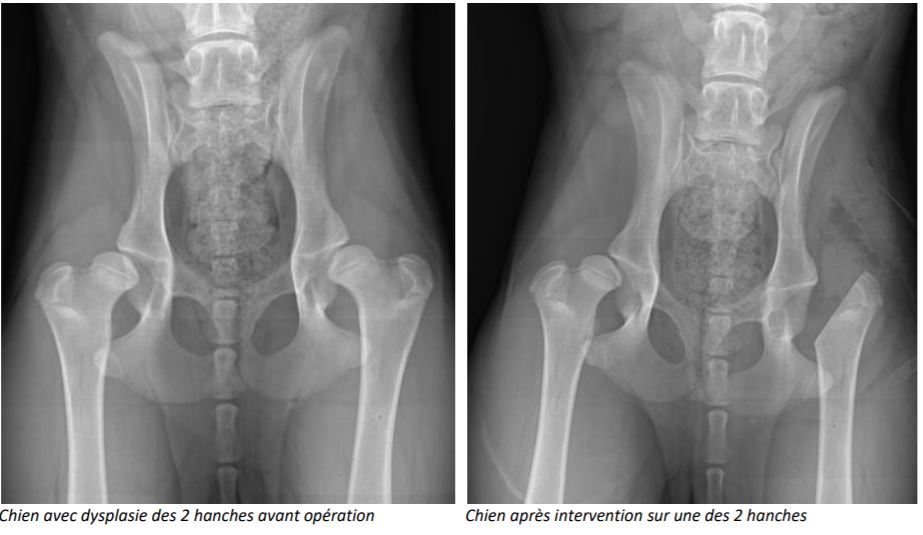

La dysplasie peut être diagnostiquée radiologiquement très tôt, vers l’âge de 5-6 mois.

En revanche, les examens systématiques officiels visant au dépistage de l’affectation sont réalisés plus tardivement, vers 12 mois.

La lecture consiste à apprécier la forme des têtes fémorales, l’enserrement de cette même tête par l’acétabulum, la congruence (rapport entre les surfaces articulaires) de l’articulation, repérer les éventuels signes visibles d’arthrose (ostéophytes,…), et la laxité de l’articulation, mesurée principalement par l’angle de Norberg Olsson.

L’exérèse de la tête fémorale peut donner de bons résultats:

La résection de la tête et du col fémoral est une intervention chirurgicale qui permet de réduire la douleur de votre animal

au niveau de la hanche. La chirurgie est particulièrement adaptée aux chiens de petits et moyens formats et aux chats.